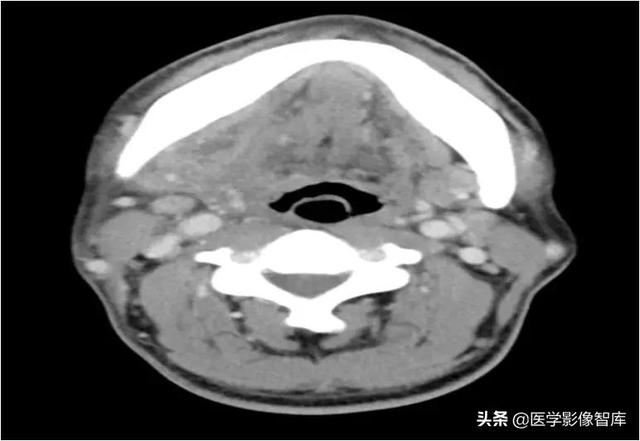

咀嚼肌间隙、颌下间隙、左侧颞下间隙,颊间隙,翼颌间隙

男,55岁,左下后牙反复肿疼1年余,加重1月余,疼痛剧烈伴张口受限,面部肿胀。

咀嚼肌间隙有脓肿形成。